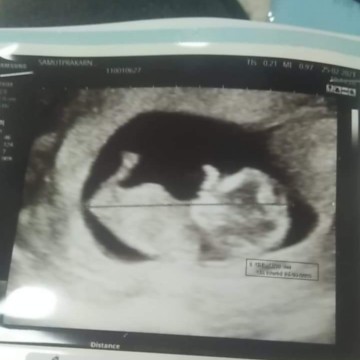

เด็ก 11 week ปกติจะเห็นชัดและตัวใหญ่แบบนี้มั้ยคะ มีแต่คนไม่เชื่อว่าน้อง 11 week คะ.

ปกติจ้า เครื่องหมอดีก็ชัดแล้วค่ะ ในภาพหมอซูมนะแม่นะ เพื่อให้แม่เห็นชัด ของเราก็ชัดกว่านี้ด้วยซ้ำ ตอนอายุครรภ์เท่ากัน

ปกติจ้า หมอซูมเพื่อให้ดูชัดขึ้น แต่ตัวน้องจริงๆช่วงไตรมาสแรกยังเล็กมากนะแม่

แค่ซูมภาพใกล้ๆค้ะเพื่อให้เห็นชัด ของจริงตัวเท่านิ้วก้อยเองค่ะ